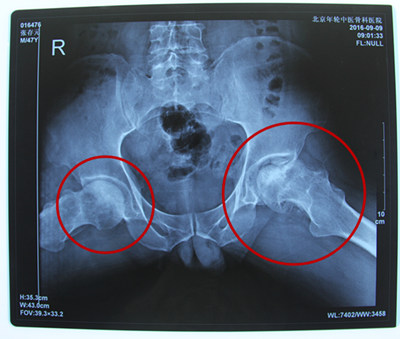

诊断结果:双侧股骨头缺血性坏死

病情描述:患者于5年前无明显诱因开始出现双髋关节腹股沟区疼痛,表现为隐痛,行走跛行,于久行及劳累后加重,就诊于当地医院,诊断为“双侧股骨头缺血性坏死”,间断口服中药药物治疗2周,左髋关节缓解不明显,2013年北京积水潭医院给予通络生骨胶囊口服治疗左侧髋关节疼痛,状况稍有好转,2016年初武警北京二院行介入治疗,效果一般。后因状况剧烈疼痛影响正常生活,选择到医院进行治疗。

2016年9月在残联的帮助下加入到了站立计划的项目中来。残联和站立计划的工作人员经实际考察发现张存元在费用支付上存在一定的困难。经特殊批准得到了站立计划的全额救助,2016年9月8日来到北京年轮中医骨科医院接受治疗。经年轮股骨头医师会诊后决定对其股骨头坏死病变区进行髋关节滑膜切除、清理并修正松解;同时取髂骨进行骨移植微创治疗,并辅以特制中医中药调理病况,由康复医师指导日常髋关节功能的恢复。